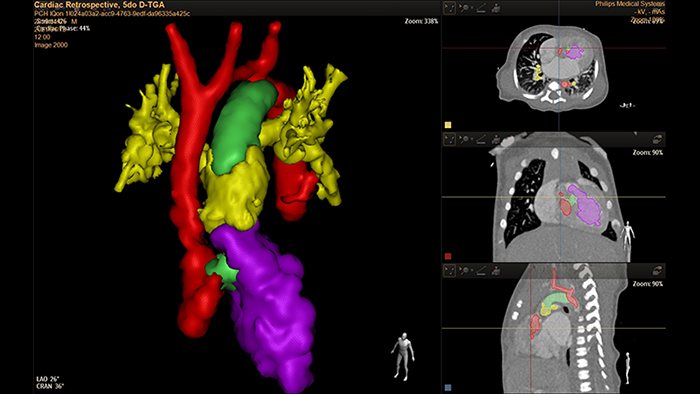

Análisis D-TGA de 5 días con HeartNavigator

Modelado 3D con IntelliSpace Portal